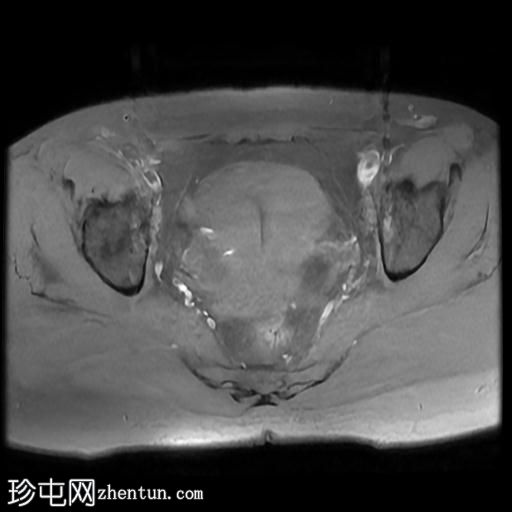

轴位

T2加权像

右侧输卵管呈管状囊性扩张,直径达30 mm,提示输卵管积水,呈均匀液体信号,无实性成分。

左侧输卵管亦有轻度扩张,直径26 mm,符合输卵管积水表现。

右侧卵巢可见一单纯性卵巢囊肿,大小约35 x 40 mm,呈正常液体等效信号。

MRI 检查结果显示双侧输卵管积水和右侧卵巢单纯性囊肿。总体而言,所有附件和盆腔检查结果均显示良性 MRI 特征(O-RADS 2 类),无恶性肿瘤迹象。